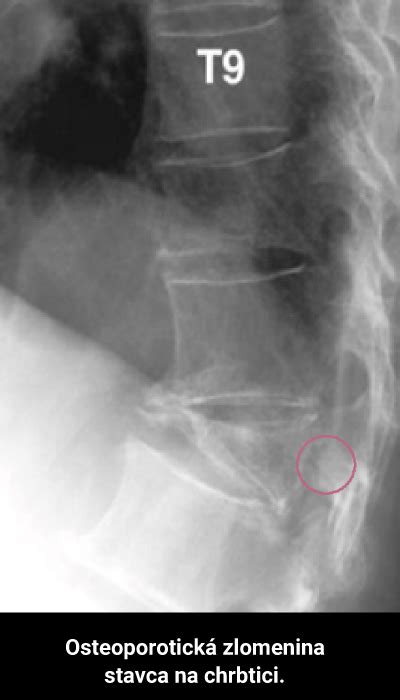

Podľa môjho osobného názoru sa nedostatok vitamínu D týka väčšiny populácie, predovšetkým v stredoeurópskych krajinách. Keďže je vitamín D zodpovedný za správnu metabolizáciu vápnika, pri jeho nedostatku sa radikálne znižuje črevná absorpcia vápnika z potravy. Dlhodobý, resp. ťažký nedostatok vitamínu D spôsobuje u detí mäknutie kostí, ktoré môže vyústiť do krivice. Kosti sú menej mineralizované, u dospelých dochádza k osteomalácii. V takýchto prípadoch môže dôjsť k ohýbaniu kostí, a to v oblasti najväčšej gravitačnej tiaže, teda v oblasti chrbtice, nôh, k ochabovaniu svalov a k zvýšeniu rizika vzniku zlomenín. Okrem osteomalácie môže dôjsť k vývoju osteoporózy, teda k zníženiu hustoty kostí, čím sa zvyšuje ich krehkosť.